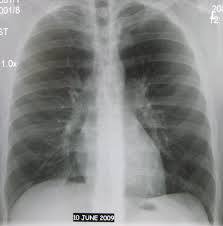

Человек обязательно должен регулярно проходить флюорографическое обследование. Такое обследование необходимо делать не реже, чем один раз в год. Многие люди отказываются от флюорографии, так как не хотят получать лишнее облучение. Но та доза облучения, которая бывает при прохождении флюорографии, не причинит такого вреда, как возможное заболевание туберкулезом. Туберкулез – это тяжело поддающееся лечению инфекционное заболевание, вызываемое специфическими микобактериями. Как правило, на полное выздоровление требуется не менее года. Ежегодно у 8-10 миллионов людей инфицированность туберкулезом переходит в заболевание, причем 75% больных составляют лица трудоспособного возраста. Эпидемиологическая обстановка по туберкулезу на территории Амурской области остается напряженной. Основным источником инфекции является человек, больной легочной формой туберкулеза и выделяющий микобактерии из дыхательных путей. Период заразности источника инфекции равен всему периоду заболевания, способного длиться годами и десятилетиями. Основные пути передачи инфекции - воздушно-капельный (с частичками мокроты, носоглоточной слизи, попадающими в воздух при кашле, чихании, разговоре) и воздушно-пылевой (с пылью в воздухе, содержащей микобактерии) |